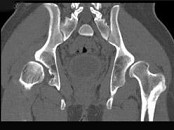

男,23岁,跛行,外展受限,两下肢不等长,结合图像,最可能的诊断是()

• A.髋关节中心脱位

• B.髋关节后脱位

• C.髋关节前脱位

• D.先天性髋内翻

• E.髋关节结核